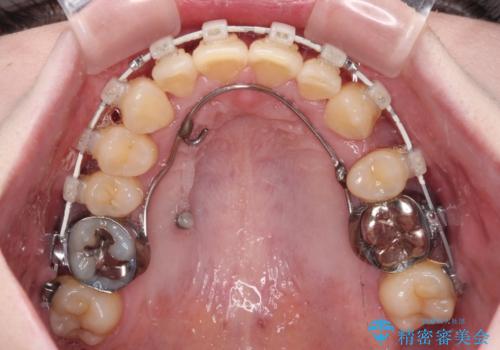

- 矯正装置

- 審美装置

上顎左側の第一小臼歯を抜歯し、補助装置を用いて正中位置を改善しながら八重歯を解消していくこととしました。

下顎前歯が1本欠損していたため、上下正中の位置が合わせるという目標はなく、鼻筋に上顎正中を合わせていくように移動を行いました。